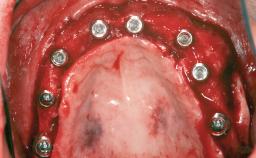

A 46-year-old woman was referred for treatment whose main complaints were mobility of her fixed partial dentures (right maxilla and left mandible) and periodontal bleeding during function. She also reported having taken systemic antibiotics to treat recurrent swelling in the area of the upper left molars. The patient had not seen a dentist for at least 2 years. She did not smoke and had no history of major systemic disease other than two minor orthopedic procedures some years back. The first-visit examination revealed poor plaque control, tooth mobility, periodontal disease, and a residual dentition widely associated with deep periodontal pockets.

# of Teeth 5

# of Implants 3

Type of Implants One-Piece

Bone Augmentation Horizontal|Staged|Vertical

Augmentation Materials Autogenous chips|Autogenous block(s)|Xenogenous